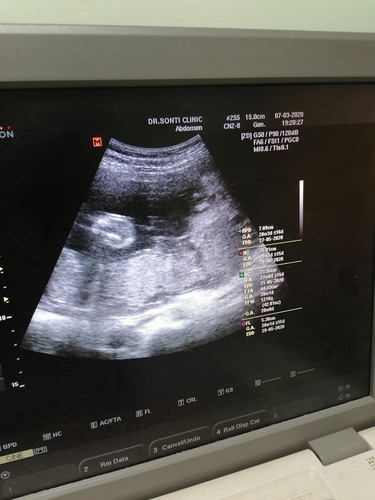

ควรยึดอันไหนเป็นหลักค้ะ กำหนดคลอดมิ.ย ตอนนี้27w1d ตรงกับที่คุณหมอที่ฝากครรภ์โรงบาล แต่วันนี้ไปซาวน์ที่คลีนิคมาในใบซาว28wกว่าแล้วค่ะ

คุณหมอจะยึดจากการซาวน์ครั้งแรกที่เห็นตัวค่ะ ไม่เกิน3เดือนจะเป็นช่วงที่ตัวอ่อนโตตามเกณฑ์ และประเมินวันคลอดได้แม่นกว่า ส่วนที่ซาวน์ตอนโตหลายเดือนแล้ว อันนี้ตามขนาดการเติบโตค่ะ